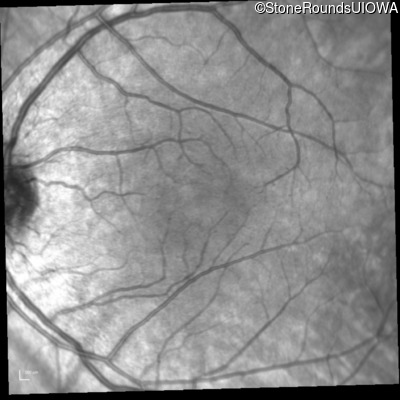

Infrared Fundus Photograph - Right - 20/25

Exemplar